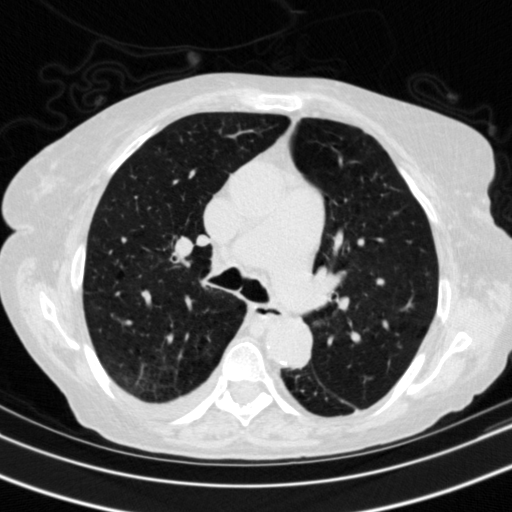

Original NATIVE CT scan (input)

Lung window (WL -600, WW 1500 β†’ Low βˆ’1350, High +150)

Mediastinum window (WL 40, WW 400 β†’ Low βˆ’160, High +240)